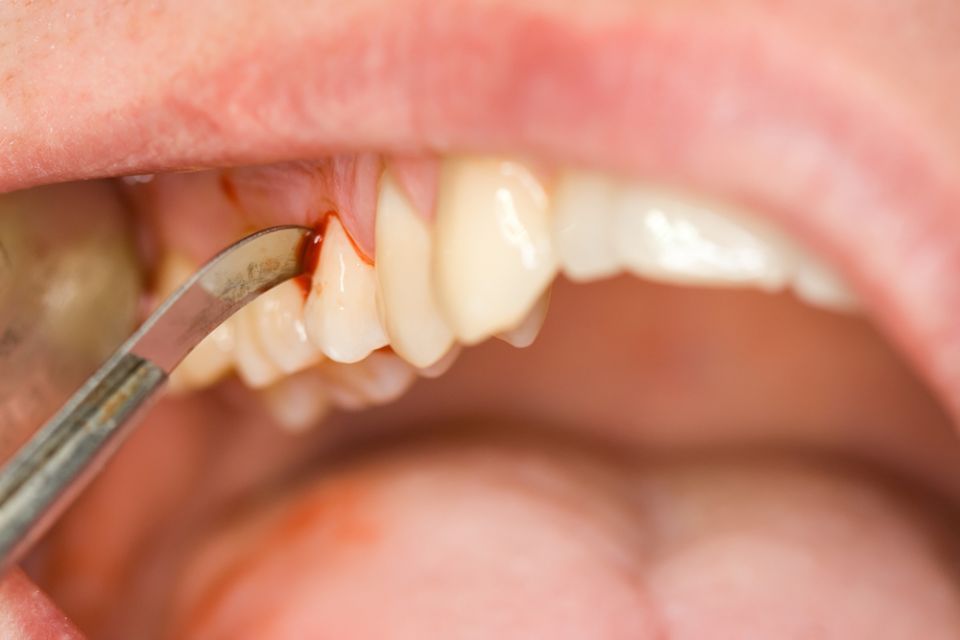

Periodoncia y cirugía periodontal

La Periodoncia es la especialidad odontológica dedicada al estudio del periodonto o la estructura de soporte de los dientes. Engloba la prevención, el diagnóstico y el tratamiento de las enfermedades que afectan a estos tejidos que rodean y sujetan el diente al hueso (encía, cemento radicular, ligamento periodontal y hueso alveolar).

Dentro de las enfermedades periodontales más conocidas encontramos:

La gingivitis que cursa con inflamación y enrojecimiento de las encías y posible sangrado al cepillado.

La periodontitis clínicamente presenta los signos de la gingivitis pero también se acompaña de la pérdida de los tejidos que soportan el diente: el ligamento periodontal y el hueso alveolar, causando la movilidad del diente y futura pérdida de éste si no se trata.

Nuestro objetivo principal es la prevención de la aparición de la periodontitis y en caso de diagnosticarse, tratarla para poder eliminar la inflamación y poder detener su progresión. Por ello, es importante que el paciente tenga un buen hábito de higiene bucal y asista a las revisiones y visitas periódicas del dentista.